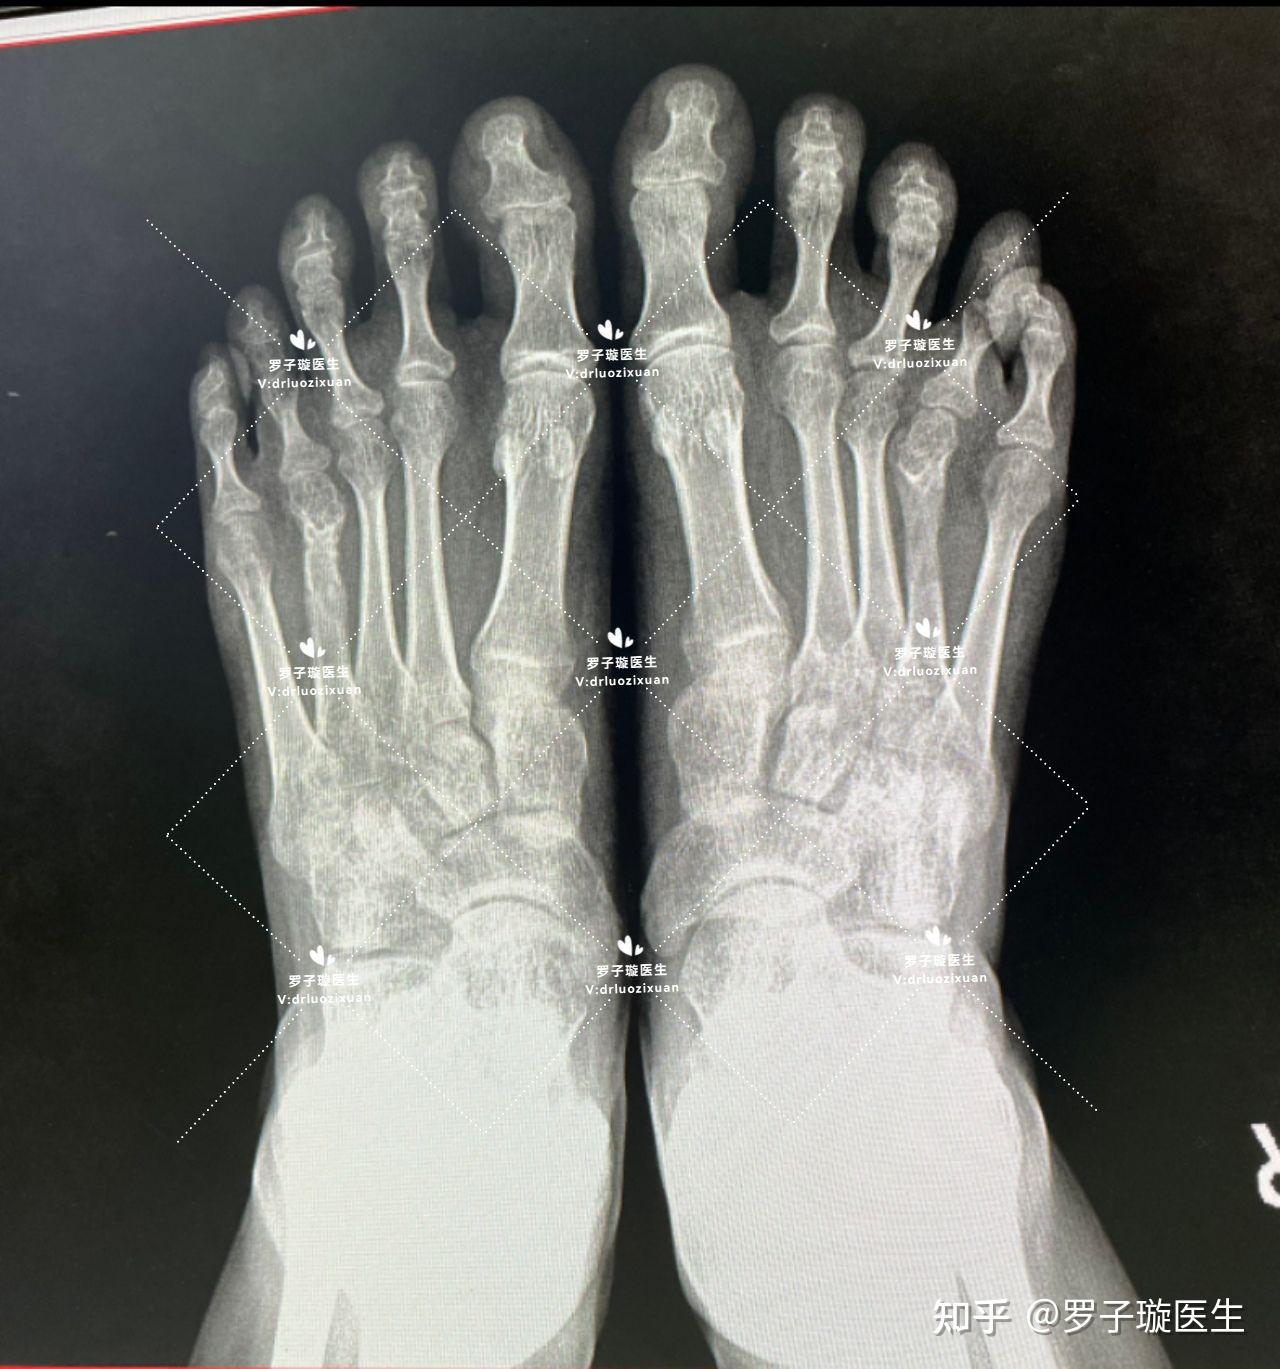

关于短趾症(脚趾短小症)手术的一些常见问题 - 知乎

图片尺寸838x777

第四脚趾短小症—短趾症—治疗过程 - 知乎

图片尺寸1280x1369